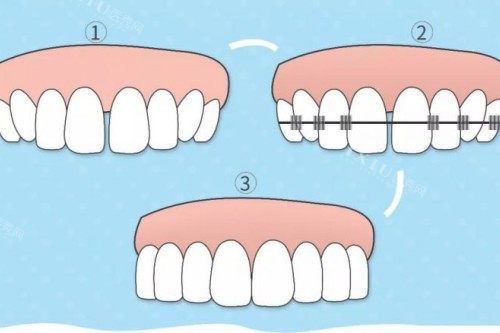

ETA 功能性矫正器主要利用儿童替牙期牙齿的生长力量,来引导恒牙正确生长,并且使已经长歪的恒牙得到有效的矫正。它就像是为牙齿铺设了一条 “精密轨道”,能扩充牙弓,使牙列排齐,调节口腔肌肉使其正常运动,从而让孩子的上下颌也正确生长。这种矫正方式更侧重于在牙齿 “长歪前” 直接介入,通过物理施力让牙列排齐,同时刺激牙弓扩张,改善颌骨发育不对称问题。

MRC 肌功能矫治器则是通过训练孩子舌头的正确位置、吞咽的正确方式和用鼻呼吸等习惯,来达到矫正牙齿的目的。它就像口腔习惯的 “私人教练”,从根本上改善口呼吸、咬唇等导致牙齿畸形的肌肉功能问题。通过训练,不仅可以带来整齐的牙齿排列,还有利于牙弓的扩张,对孩子的颌面部发育也非常有利。